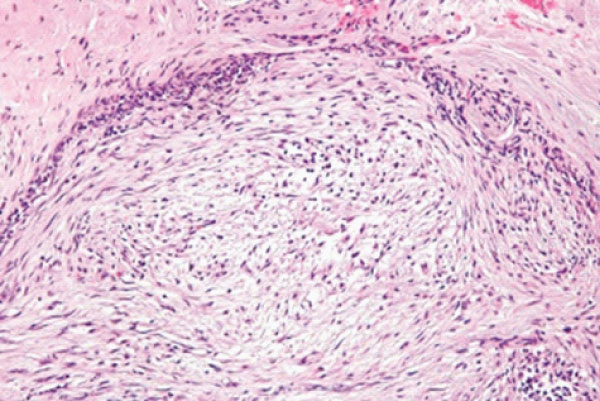

Upon microscopy, the variably cellular tumefaction enunciates a myxoid to collagenous extracellular matrix with foci of cystic degeneration. Ancient lesions are preponderantly collagenous [1,2]. Tumefaction is comprised of spindle–shaped or stellate cells imbued with indistinct cytoplasm and bland, elliptical nuclei. Neoplastic cells configure a loose, fascicular or storiform pattern, designated as ‘tissue culture–like’ or ‘feathery’ growth pattern. Mitotic activity is significant although atypical mitotic figures are absent. Red cell extravasation is frequent [1,2]. Tumour parenchyma is intermingled with an inflammatory exudate composed of disseminated lymphocytes, histiocytes or osteoclast–like giant cells [1,2]. Upon ultrastructural examination, characteristic features of fibroblasts, peripheral, longitudinal myofilaments and hemidesmosome–like structures can be discerned [1,2].

Figure 1: Nodular fasciitis demonstrating fascicles of spindles–shaped cells with uniform, ovoid nuclei and circumscribing fibrotic stroma with minimal mitosis [5].

Figure 2: Nodular fasciitis delineating bundles of stellate and spindle–shaped cells with uniform, elliptical nuclei and encompassing fibrotic stroma [6].